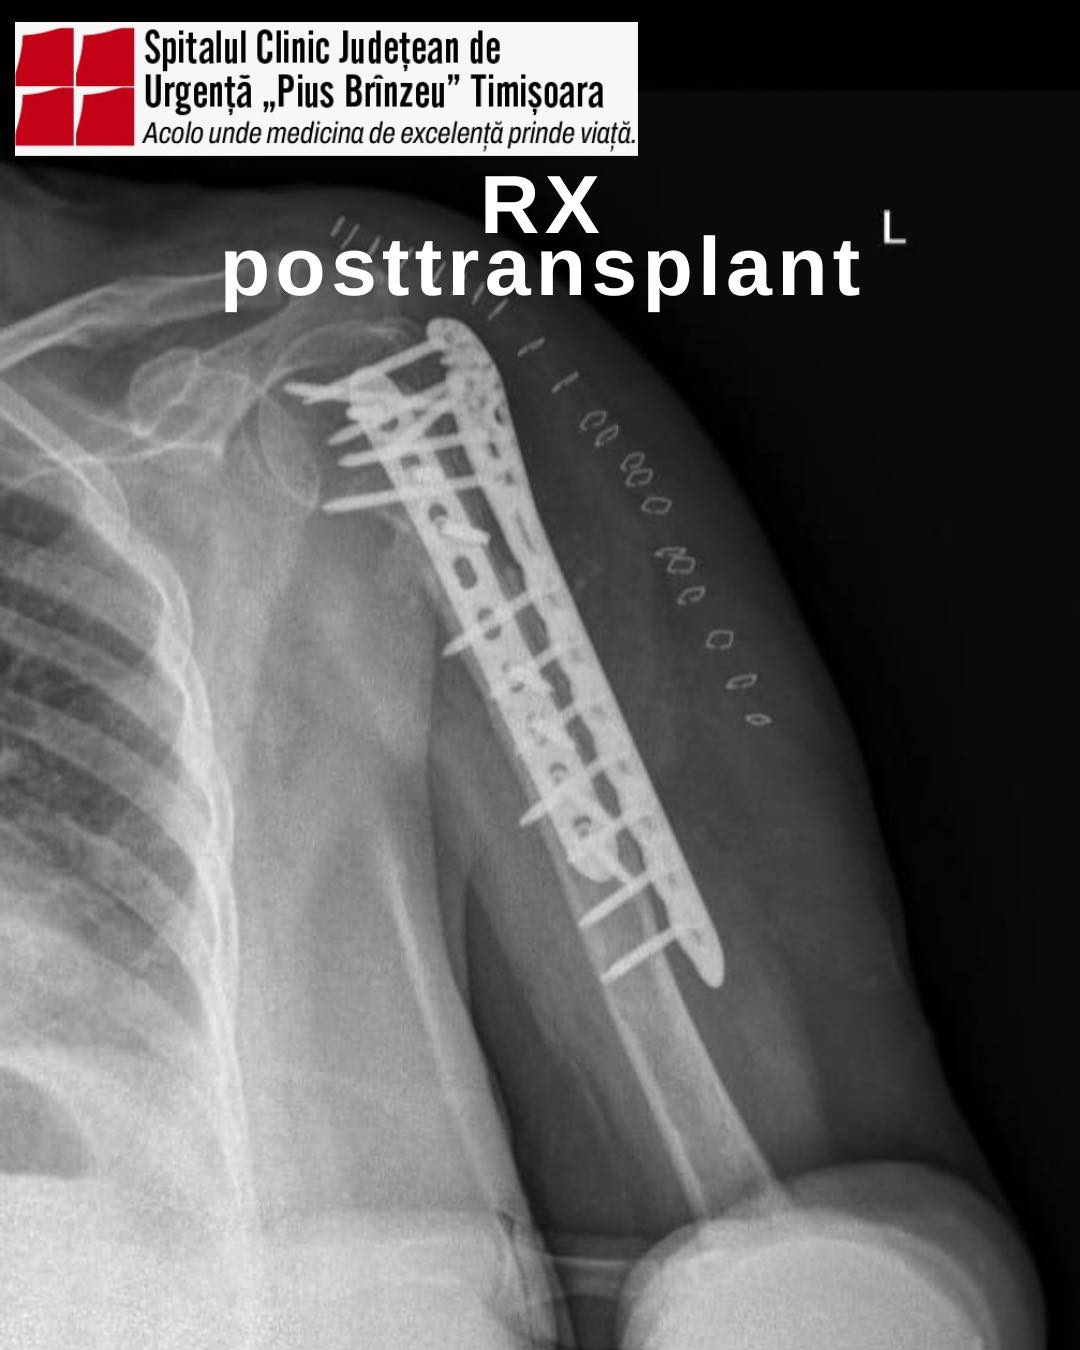

Intervenția a constat în augmentare biologică, mai exact refacerea osului cu ajutorul unei grefe de os preluată de la un donator, urmată de fixare internă prin tehnica „double plating”, o metodă modernă care folosește două plăci metalice pentru a stabiliza osul.

Grefa osoasă a fost asigurată de Banca de Os a Spitalului Colentina, în cadrul unei colaborări interinstituționale. Echipa spitalului i-a mulțumit doctorului Andrei Nica, responsabil al băncii de țesut musculo-scheletal, pentru sprijinul acordat și profesionalismul constant.